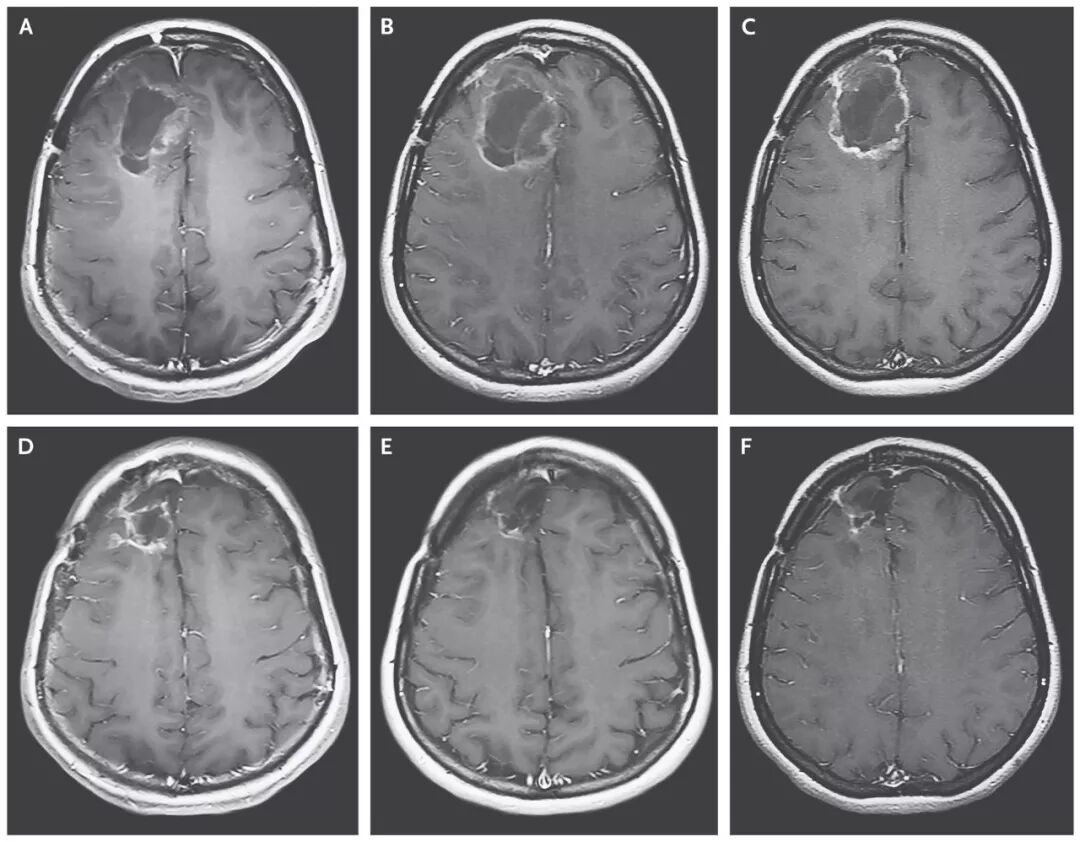

溶瘤病毒创造恶性脑瘤完全缓解的治疗奇迹!

截止2018年3月20日,8名患者对治疗产生治疗应答,2名患者的脑胶质瘤病灶完全消失,达到了完全缓解!

▲患者脑部肿瘤的缩小清晰可见(图片来源:《NEJM》)

这位患者,经过PVSRIPO溶瘤病毒治疗7个月后,病情复发后使用洛莫司汀治疗,经过12个月的洛莫司汀治疗后,病人的病灶完全消失并保持了20个月的无病状态,并且在PVSRIPO溶瘤病毒治疗发生出血后57.5个月仍然存活。